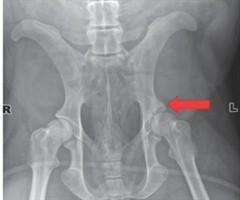

大熊猫白病理性骨折的病例分析

稿件运行过程 收稿日期:2025-04-9 修回日期:2025-0-27 Keywords:Giant panda (Ailuropoda melanoleuca); Acetabulum; Pathological fracture; O...